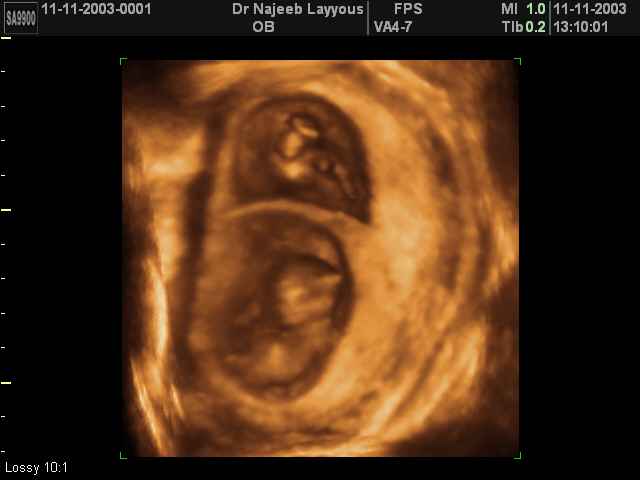

- لقطات فيديو للجنين بجهاز الموجات فوق صوتية رباعي الأبعاد

- صور للجنين في المراحل الأولى من الحمل

- صور لتوائم

صور لتوائم بجهاز الالتراساوند ثلاثي الأبعاد | الدكتور نجيب ليوس